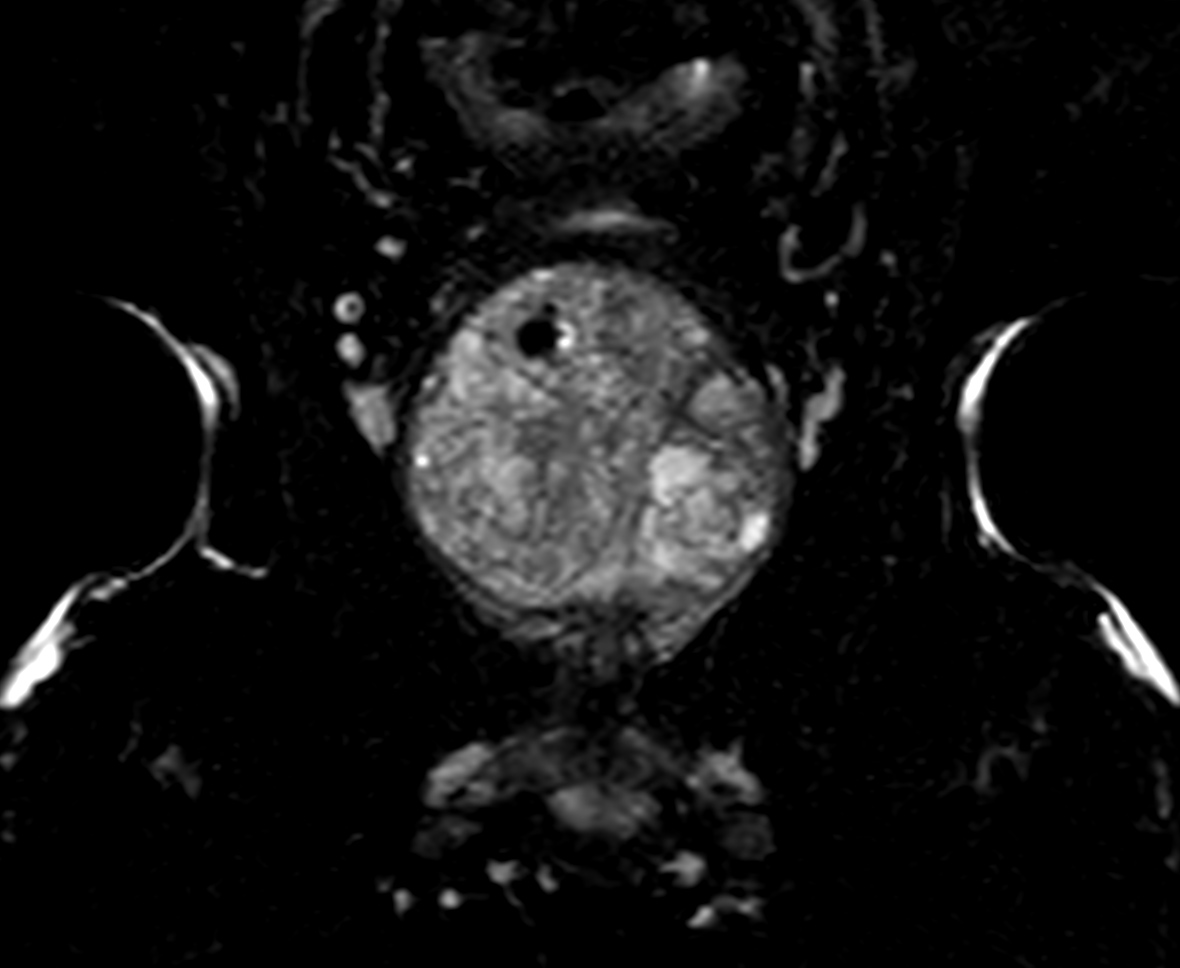

DWI b1000 (ADC)

-